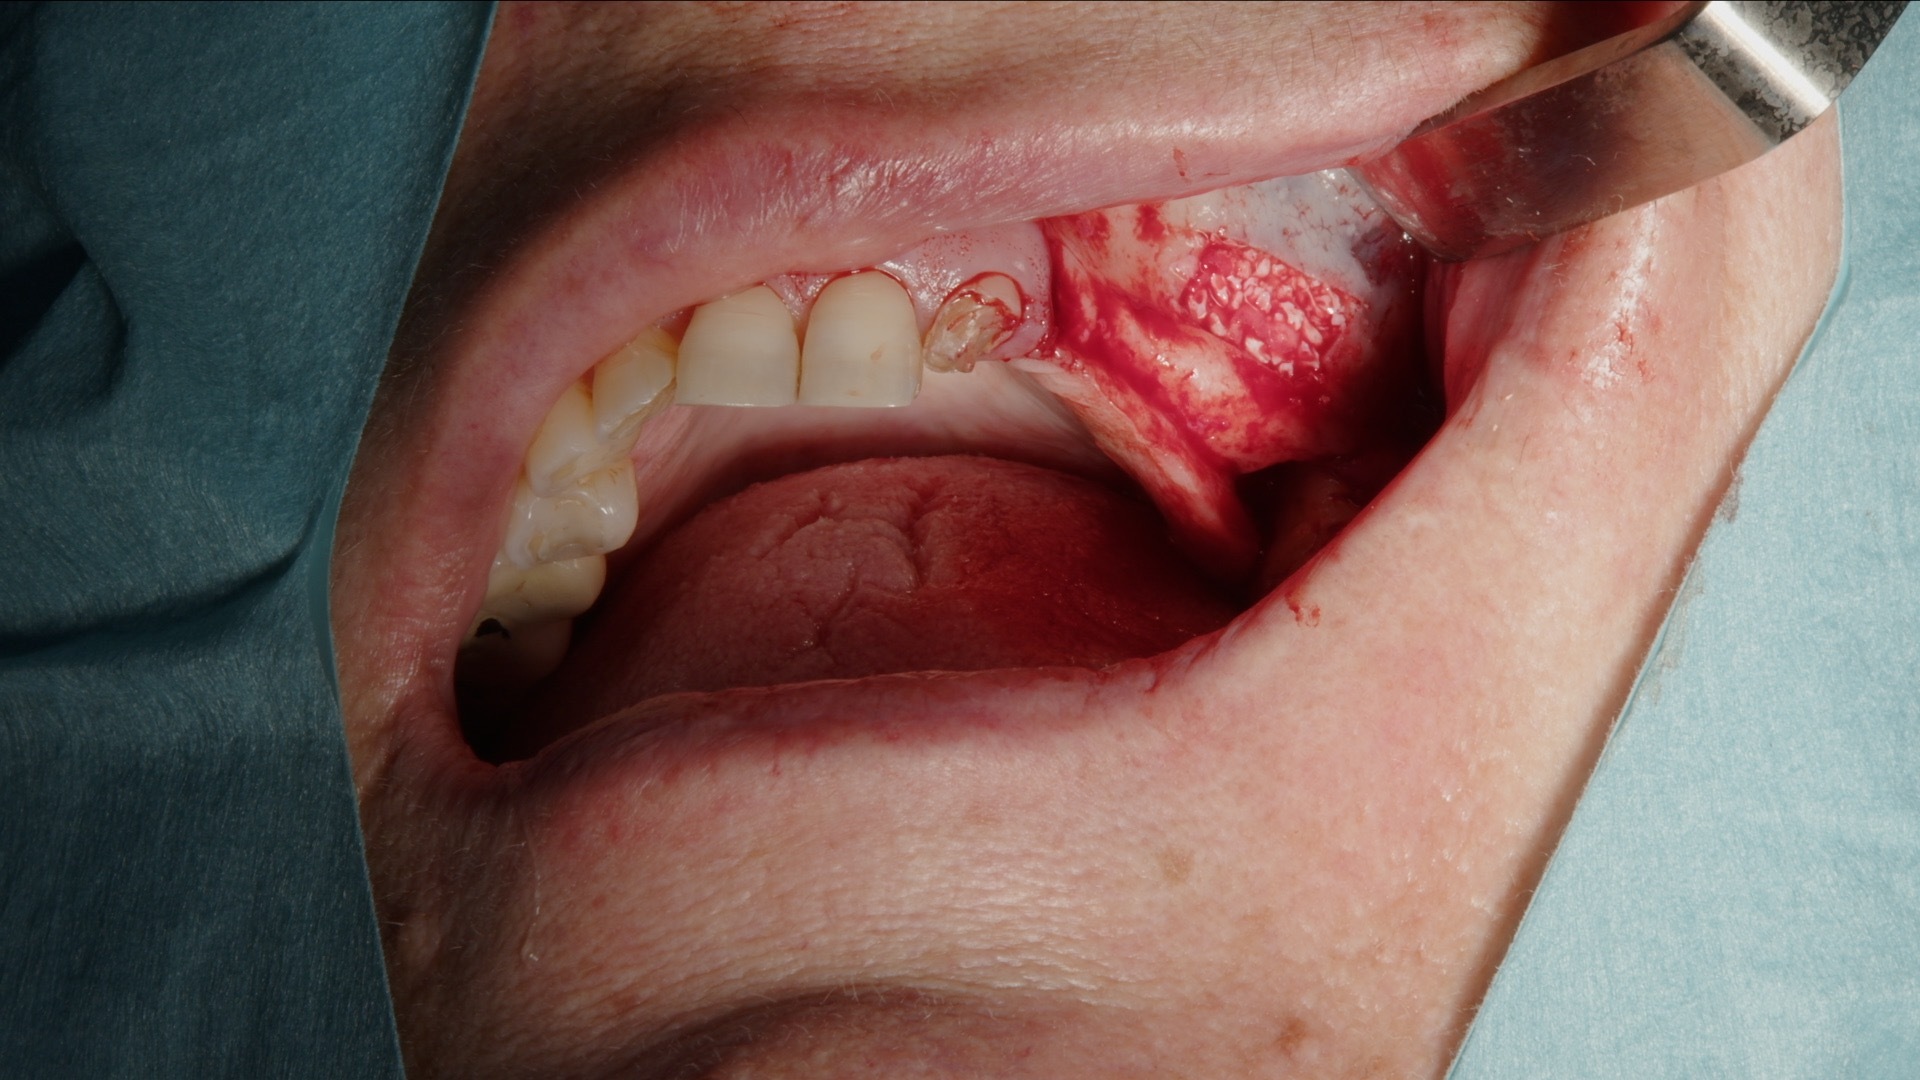

Autologt ben høstes med Safescraper direkte fra operasjonsområdet. Metoden er minimalt invasiv og gir vitalt benmateriale med høy biologisk potensial. Det autologe benet blandes deretter med Geistlich Bio-Oss for å skape en stabil graftmasse med både osteokonduktive og osteoinduktive egenskaper.

Den ferdige blandingen plasseres systematisk i det etablerte sinusrommet til ønsket volum er oppnådd. Kombinasjonen gir god vaskularisering, langsiktig volumstabilitet og forutsigbar benregenerasjon.

5. Utfylling med blanding av Geistlich Bio-Oss og autologt ben.

6. Fullstendig augmentert sinusrom.